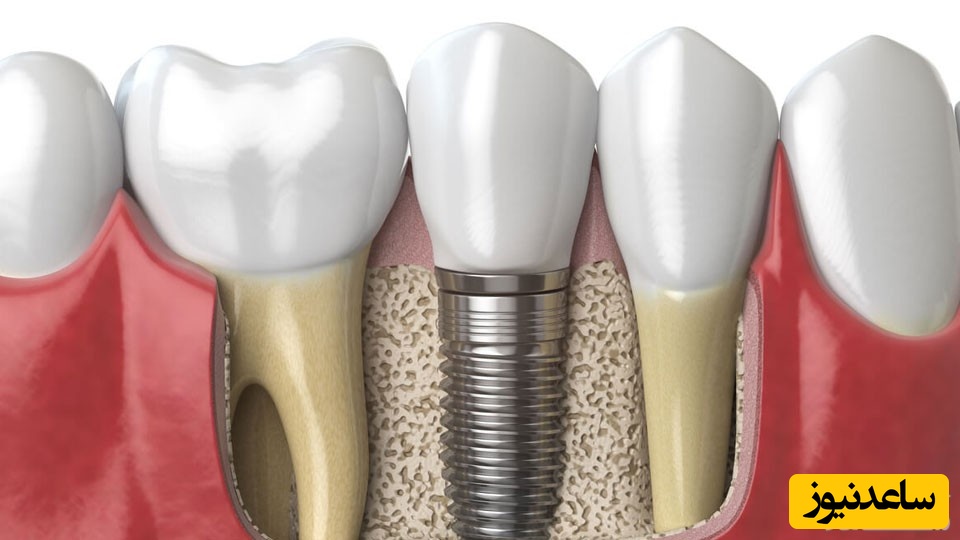

به گزارش سرویس سلامت ساعدنیوز، پیوند استخوان در ایمپلنت دندان، عمل پیوند استخوان در سینوس های فک برای ایجاد یک بستر مناسب جهت کاشت ایمپلنت است. پیوند استخوان در ایمپلنت دندان در افرادی صورت می گیرد به دلیل ضعف در استخوان فک امکان کاشت دندان جدید برایشان وجود ندارد. برای معرفی یک عمل پیوند استخوان در ایمپلنت دندان می توان به سینوس لیفت اشاره داشت. با اندازه گیری فاصله سطح استخوان فک تا سینوس بالای دندان می توان نوع عمل پیوند استخوان برای ایمپلنت دندان را مشخص کرد. اینکه عمل ایمپلنت به پیوند استخوان نیاز داشته باشد یا ایمپلنت بدون پیوند استخوان صورت گیرد کاملا به وضعیت استخوان فک بستگی دارد.

جالب است بدانید که اگر دندان خود را از دست دهید، پس از مدتی متوجه خواهید شد که استخوان در آن قسمت از دست رفته است. نوعی از استخوان که به طورمعمول دچار مشکل می شود، استخوان آلوئول نام دارد. وظیفه استخوان آلوئول حمایت و نگه داشتن دندان ها است. درصورتی که دندان وجود نداشته باشد، استخوان آلوئول به دلیل کمبود کار شروع به آتروفی می کند. علاوه بر این خوب است بدانید که استخوان فک با هر بار جویدن غذا، تقویت می شود. از دست دادن استخوان آلوئول می تواند به سرعت منجر به از دست دادن استخوان فک نیز شود. به یاد داشته باشید ایمپلنت های دندانی برای موثر بودن، به استخوان سازی متکی هستند؛ یعنی کاشت باید با استخوان پیوند بخورد تا یک پایه ثابت برای تاج ایجاد کند. اگر استخوانی برای کار وجود نداشته باشد، قرار دادن ایمپلنت غیرممکن می شود.